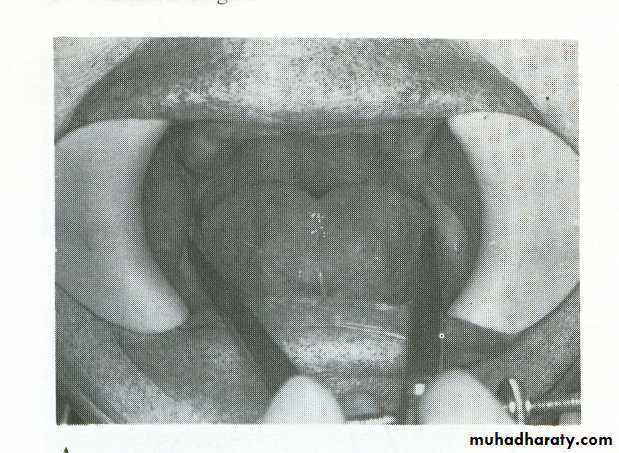

(Mandibular impression with alginate)